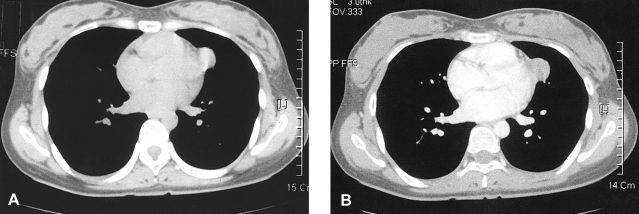

A 25-year old woman was referred to our hospital for evaluation of an abnormal chest radiograph. There was no prior family history of respiratory or salivary problems and she had no respiratory or salivary gland symptoms. The laboratory studies, including the peripheral blood counts and biochemical examinations, showed no abnormalities. The tumor markers were found to be within the normal ranges. The results of the pulmonary function tests and bronchoscopic examination were all normal. A chest radiograph showed the presence of a solitary pulmonary nodule that blunted the left cardiac border in the left lung field. A non-enhanced CT scan revealed the existence of a 2.5 × 2 cm, mild cystic mass abutting the mediastinum, which had the appearance of a pericardial or dermoid cyst (Figure 1A). Contrast-enhanced CT scans showed a mildly enhancing nodule with a well defined margin; this had the appearance of a fried egg (Figure 1B).

Figure 1

(A) The non-enhanced CT revealed a 2.5 × 2 cm, mild cystic lung mass near the mediastinum. (B) The contrast-enhanced CT scans showed a mildly enhancing nodule with well defined margin; this had the appearance of a fried egg.

In our case, it was very difficult to differentiate between a peripheral lung mass and a mediastinal mass on the radiographs because the tumor was located in the peripheral lung near the mediastinal pleura and it had the appearance of a fried egg. The contrast-enhanced CT scans showed a mildly enhancing nodule with a well defined margin; the appearance was similar to that of a benign mediastinal nodule. For a case like this, pathologic confirmation should be performed when abnormal radiographic findings are detected. However, several diverse possibilities for the differential diagnosis, including pulmonary pleomorphic adenoma, should be considered before conducting invasive diagnostic procedure.